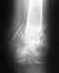

Топорова Елена Николаевна, 40 лет, 12 июня сего года без особой нагрузки произошел вывих левого коленного сустава с сильными болями. В 24 больнице были предприняты две попытки вправить сустав, одна из которых под наркозом, но до конца вправить не удалось. Предложили операцию. От операции я отказалась, т.к. существует ряд осложняющих ситуацию обстоятельств.

Я - инвалид 1 группы. Краткий анамнез: родилась с ягодичным предлежанием, во время родов пострадал шейный отдел позвоночника, были сломаны обе ключицы. В результате – спастический тетрапарез. Самостоятельно я никогда не передвигалась - только при поддержке и при помощи инвалидной коляски.Слабый связочный аппарат, суставы имеют патологическую подвижность. Коленный сустав правой ноги уже несколько лет при незначительной нагрузке выпадает и самостоятельно возвращается на место. Последнее время ситуация усугубилась тем, что повысилась спастика и обострилась хроническая грыжа поясничного отдела позвоночника.При текущем состоянии мышечно-связочного аппарата я опасаюсь, что оперативное вмешательство устранит проблему лишь на время, а потом, при моем состоянии, нет гарантии, что ситуация не повторится. В настоящее время на 4 недели наложена лангета. Сохраняются умеренные боли даже без нагрузки. Держится температура 37,4 . Имеются рентгеновские снимки до и после попытки вправления вывиха. Я бы хотела узнать, есть ли необходимость операции в моем положении, что меня ждет после оперативного вмешательства? Если жить с невправленным коленом, то это грозит только болевым синдромом (который я готова терпеть, только бы не остаться совсем лежачей) или могут развиться дополнительные осложнения, не связанные с болью? Есть ли такая жесткая необходимость оперироваться? Или можно как-то мало-мальски реабилитироваться без оперативного вмешательства?При выписке из больницы врачом была дана рекомендация пользоваться в дальнейшем самым жестким наколенником. Другим врачом через пару дней эта рекомендация была опровергнута – дескать, если наколенник, то только мягкий. Как разобраться в этих взаимоисключающих советах? С уважением, Елена Топорова.